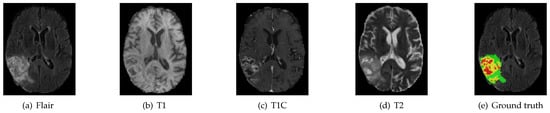

Glioma originates from glial cells in the brain and has become one of the most terrible diseases that harm human health. Glioma is a high-risk adult brain tumor, with an annual incidence of about 3 to 8 cases per 100,000 people. Medical imaging examinations, such as MRI, play a key part in the diagnosis process of brain tumors [1]. Different forms of MRI images can provide supplementary information for the analysis of different subregions of glioma. Segmentation of brain tumors in multi-modal MRI images has always been a hot research topic. These structural MRI images have positive significance in the majority of cases and the radiologist must take all the four modalities into account to identify each region. There are four standard MRI modalities: fluid attenuated inversion recovery (FLAIR), T1-weighted (T1), T1-weighted contrast-enhanced (T1C) and T2-weighted (T2). Clinically, an accurate segmentation image of brain tumor performs an indispensable role in patient care and evaluation [2]. Automatic segmentation of brain tumors can provide accurate and valuable solutions to further analyze and monitor tumors.

We evaluate our algorithm on the BraTS 2018 challenge dataset against the state-of-the-art methods. We introduce the dataset as follows. The multi-modal 3D MRIs are provided by the BraTS 2018 challenge [3,28,29]. The training data consist of 75 low grade and 210 high grade gliomas. Each subject has FLAIR, T1, T1C and T2 MRI scans, and even ground truth (GT) obtained by hand segmentation from experts. The multi-modal 3D MRIs originated from 19 institutions and employed different protocols, magnetic field strengths and MRI scanners [30]. Annotations include 4 tumor subregions: the normal tissue (label 0), necrotic and non-enhancing tumor (label 1), peritumoral edema (label 2) and active/enhancing tumor (label 4). The annotations are combined into 3 nested subregions. WT, TC and ET refer to the regions of whole tumor (label1, label2, label4), tumor core (label1, label4) and enhancing tumor (label4), respectively, as shown in Figure 4.